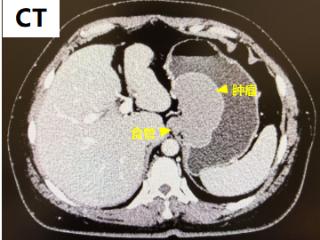

消化道肿瘤MDT+双镜联合手术!解决胃内8cm肿瘤,还保住了这两个“关键门”……